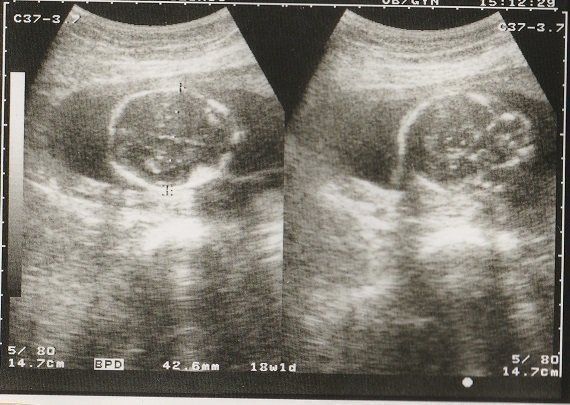

ちゃじゅびさんの妊娠18週目のエコー写真 画像におさまらないほどに成長する

赤ちゃんがどんどん大きくなり、1枚の超音波画像ではおさまりきらなくなりました。画像を2枚くっつけて赤ちゃんの大きさを測っています。

BPD(児頭大横径=頭の直径)を測って、胎児の発育を調べるようです。ここまで、母子ともに特に異常も無く過ごせました。